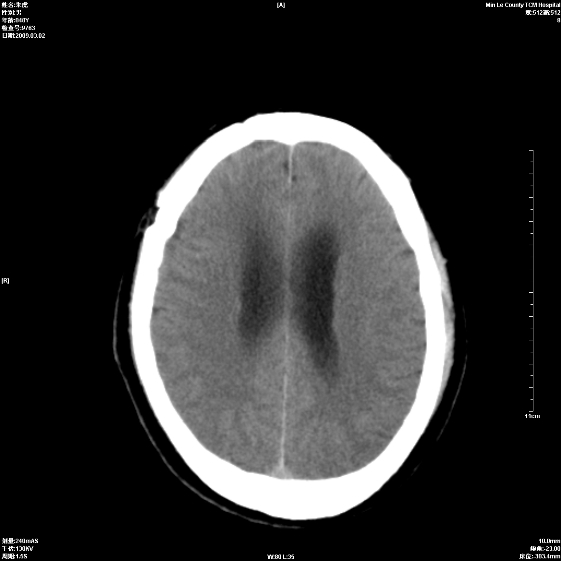

标题: CT18444:男颅咽瘤术后一月复查脑积水增多 [打印本页]

标题: CT18444:男颅咽瘤术后一月复查脑积水增多

右侧额叶局软化灶,梗阻性脑积水。

右额叶软化灶。梗阻性脑积水。

手术后改变

1、右额叶脑软化

2、脑积水

1)右侧额颞部颅骨术后改变。2)右侧额颞叶脑软化灶。3)脑积水(梗阻性)。

手术后改变1、右额叶脑软化2、梗阻性脑积水。